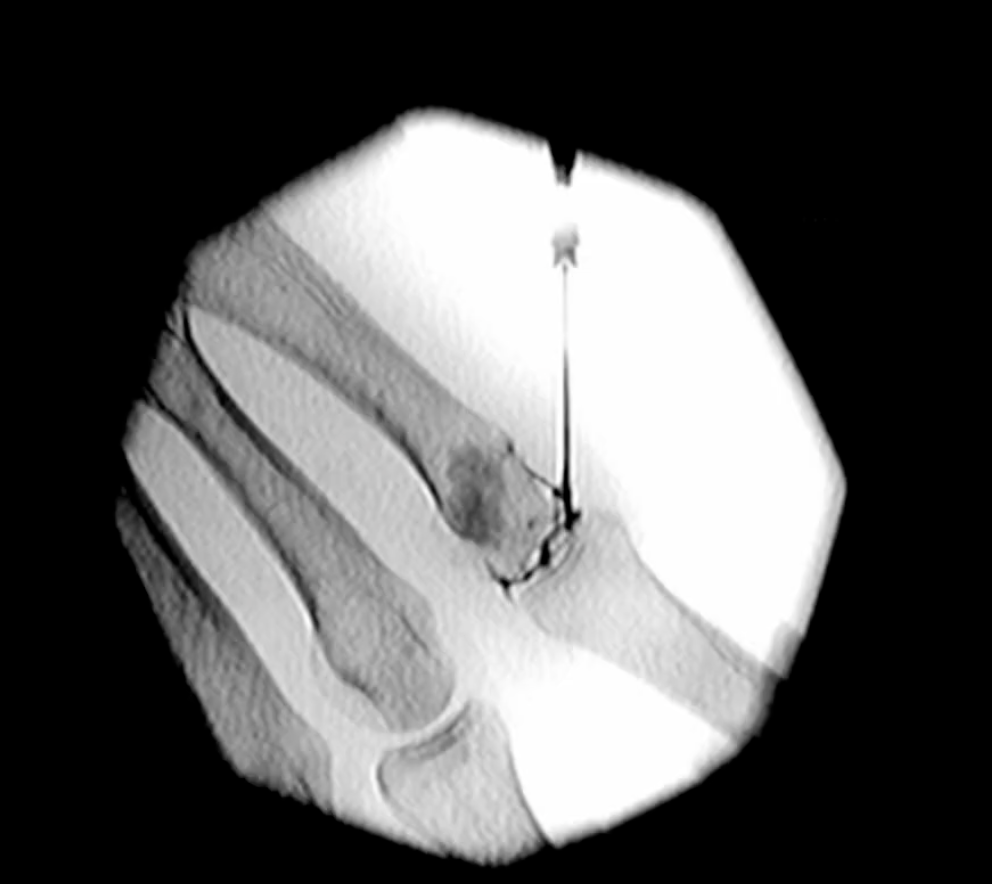

Ραδιοϋμενόλυση: Μια Σύγχρονη Θεραπευτική Προσέγγιση

Η ραδιοϋμενόλυση αποτελεί θεραπεία της Πυρηνικής Ιατρικής και εφαρμόζεται διεθνώς από τη δεκαετία του 1980, ενώ είναι αναγνωρισμένη και στην Ελλάδα (ΕΟΠΥΥ).

Η μέθοδος εφαρμόζεται τοπικά στην πάσχουσα άρθρωση, συνήθως μία μόνο φορά, χωρίς να επιβαρύνεται ο υπόλοιπος οργανισμός. Μπορεί να χρησιμοποιηθεί ακόμη και σε μικρά παιδιά. Το φάρμακο αποσυντίθεται σε λίγες ημέρες, ενώ η μείωση της φλεγμονής και των συμπτωμάτων παρατηρείται μέσα σε μερικές εβδομάδες.